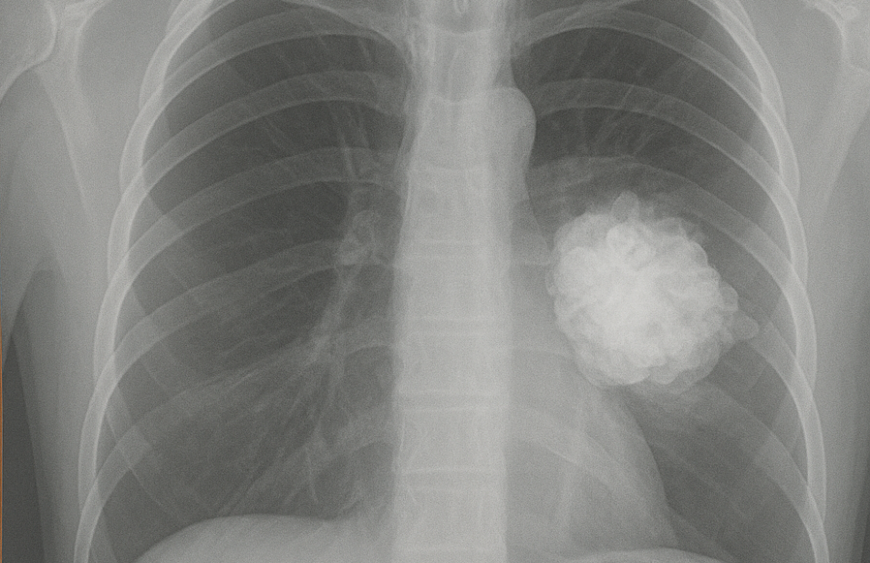

- Câncer de pulmão de células não pequenas (CPCNP) em estágio avançado, quando o tumor tem expressão de PD-L1.